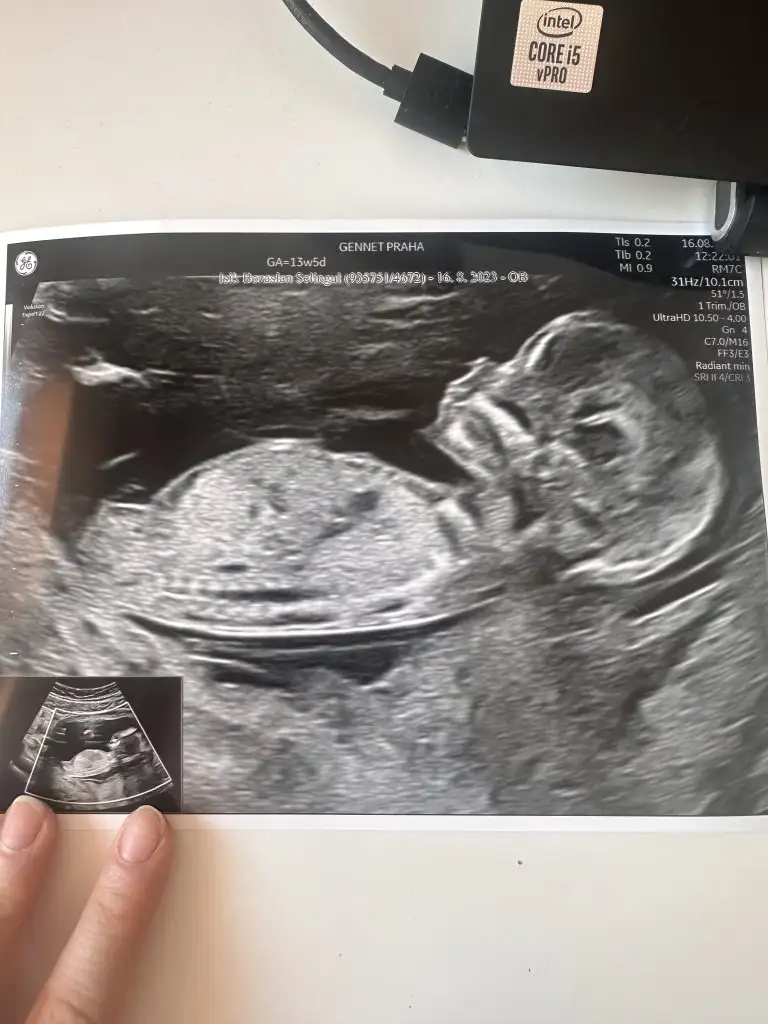

Cinsiyet tahmini 🐣

Kizlarrr sizce benim minik ne olacak 🥲